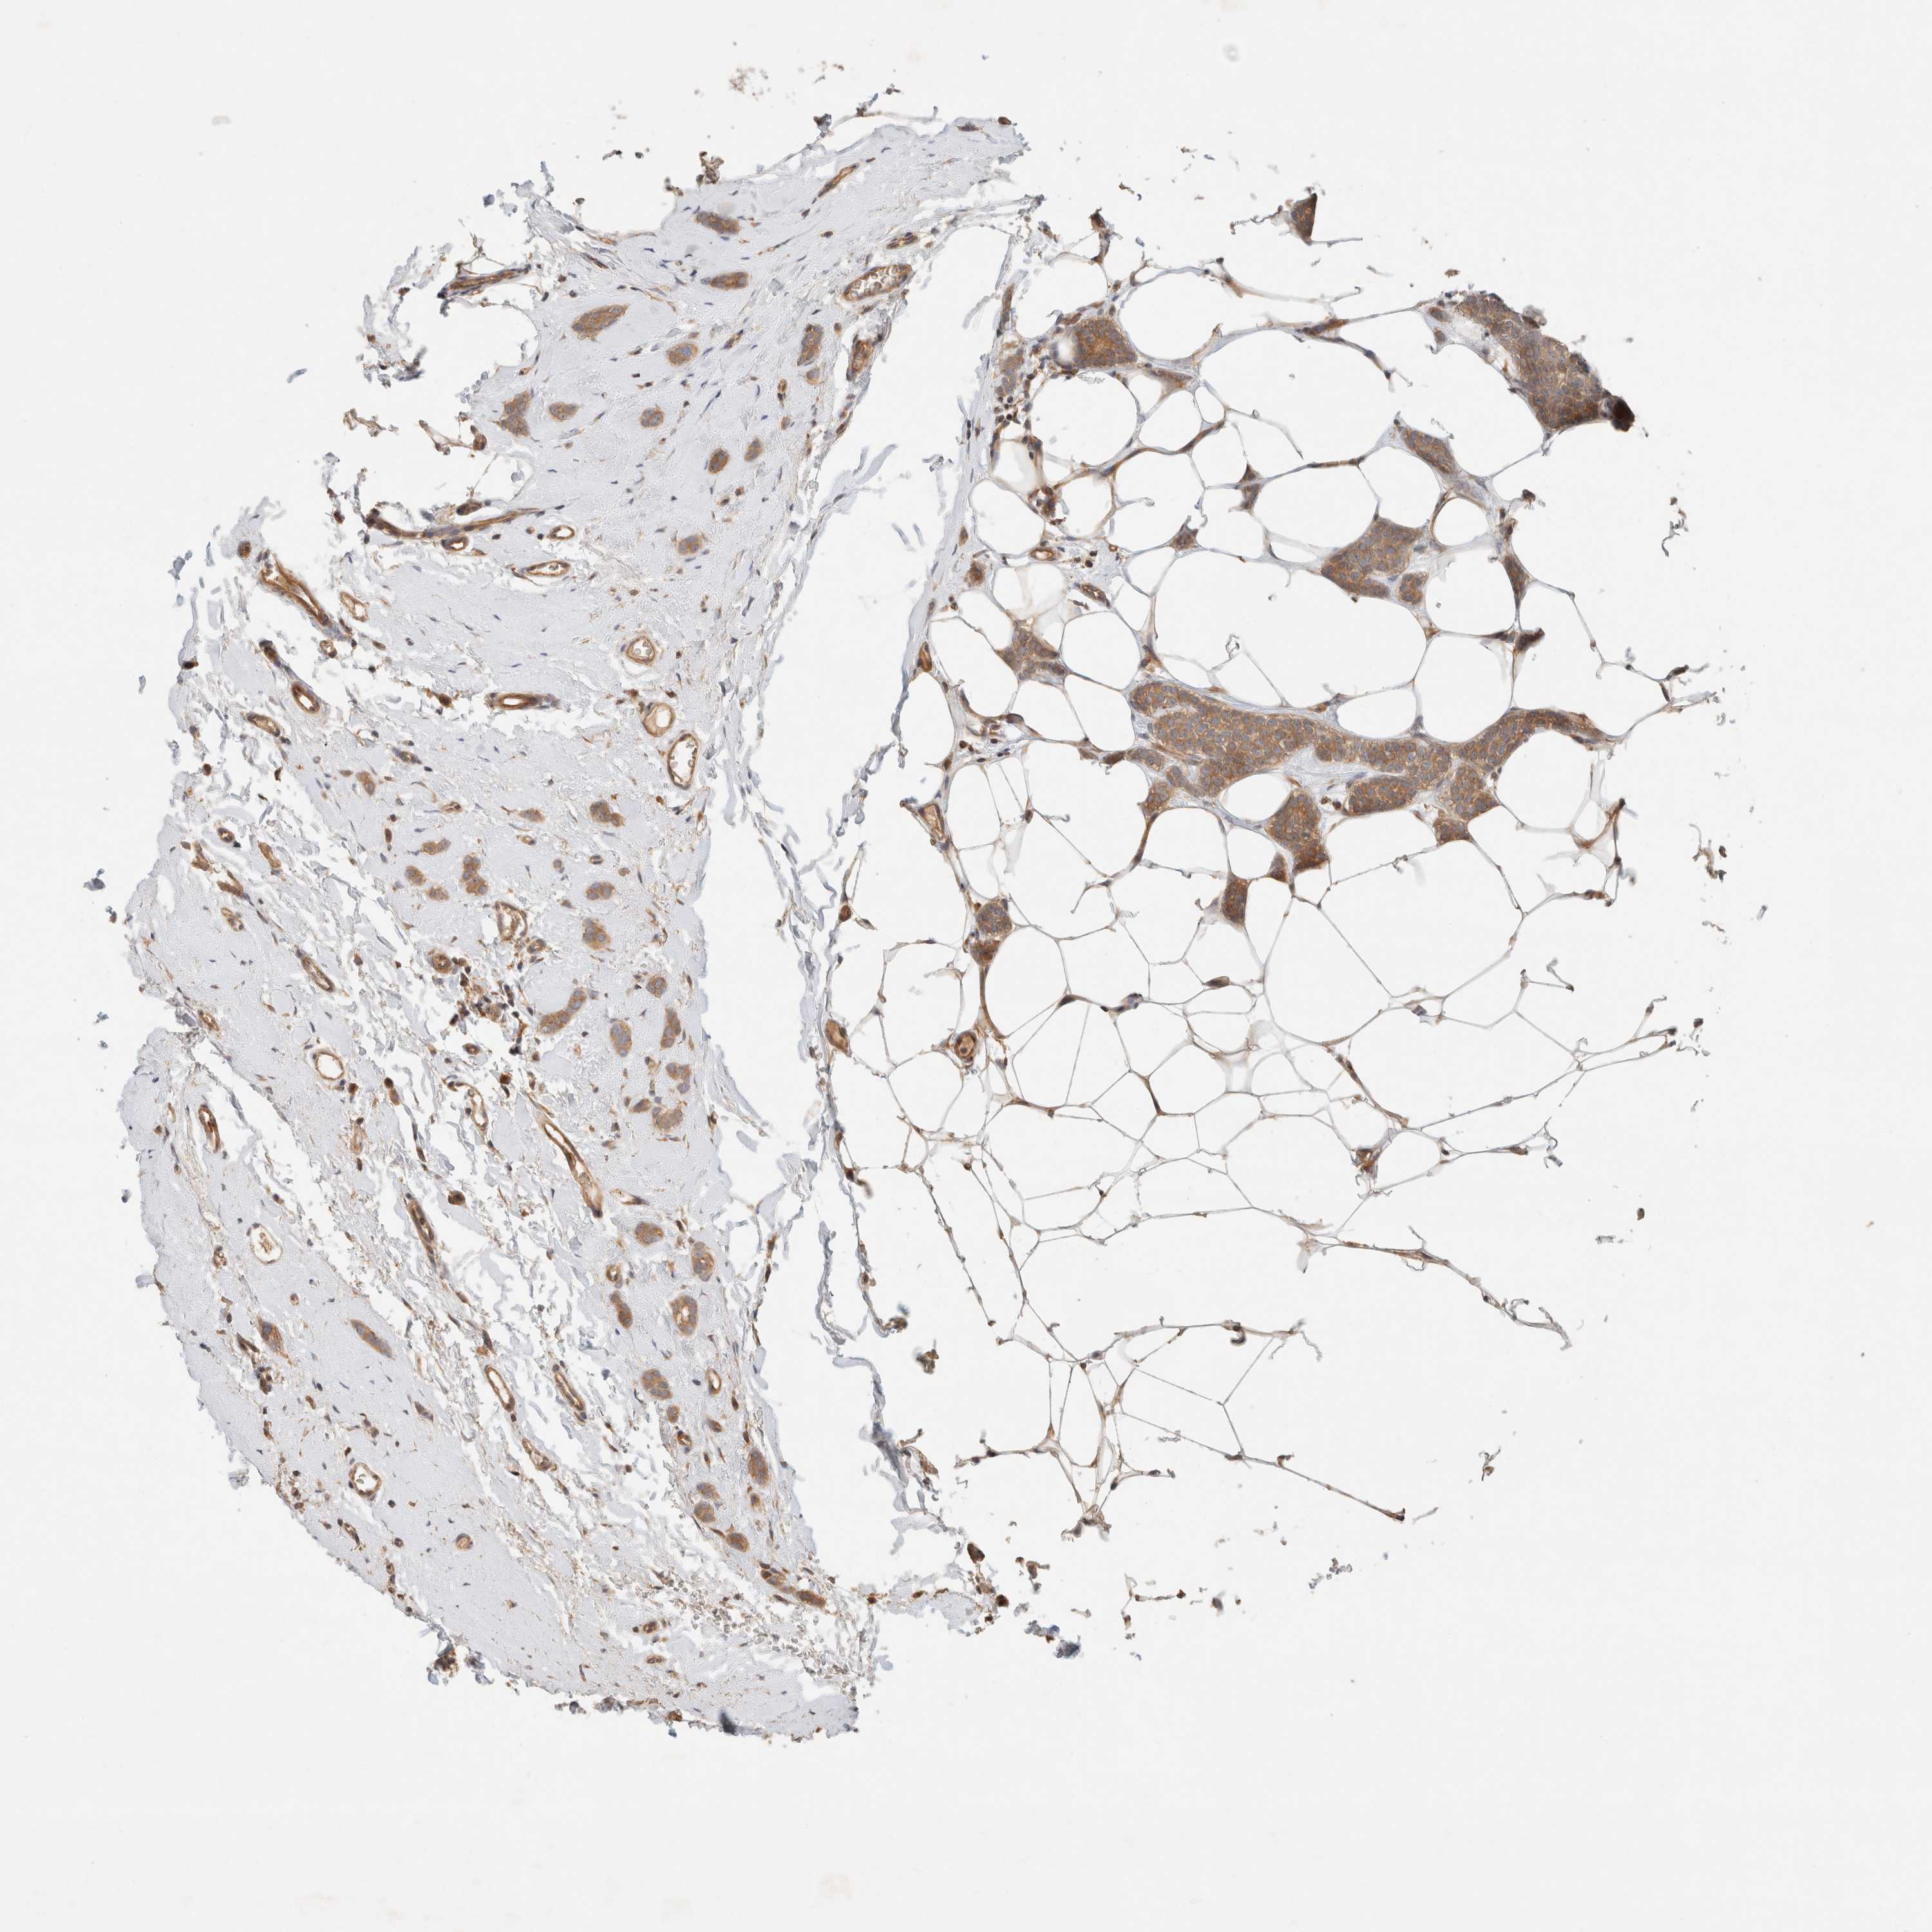

BRCA TCGA BRCA VALIDATION PROTEIN EXPRESSION

ANTIBODIES

AND

VALIDATION